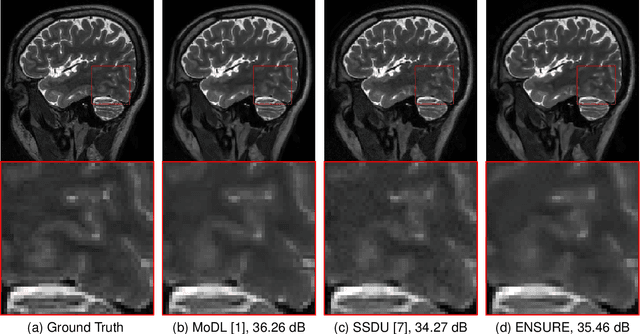

Abstract:Deep learning accelerates the MR image reconstruction process after offline training of a deep neural network from a large volume of clean and fully sampled data. Unfortunately, fully sampled images may not be available or are difficult to acquire in several application areas such as high-resolution imaging. Previous studies have utilized Stein's Unbiased Risk Estimator (SURE) as a mean square error (MSE) estimate for the image denoising problem. Unrolled reconstruction algorithms, where the denoiser at each iteration is trained using SURE, has also been introduced. Unfortunately, the end-to-end training of a network using SURE remains challenging since the projected SURE loss is a poor approximation to the MSE, especially in the heavily undersampled setting. We propose an ENsemble SURE (ENSURE) approach to train a deep network only from undersampled measurements. In particular, we show that training a network using an ensemble of images, each acquired with a different sampling pattern, can closely approximate the MSE. Our preliminary experimental results show that the proposed ENSURE approach gives comparable reconstruction quality to supervised learning and a recent unsupervised learning method.